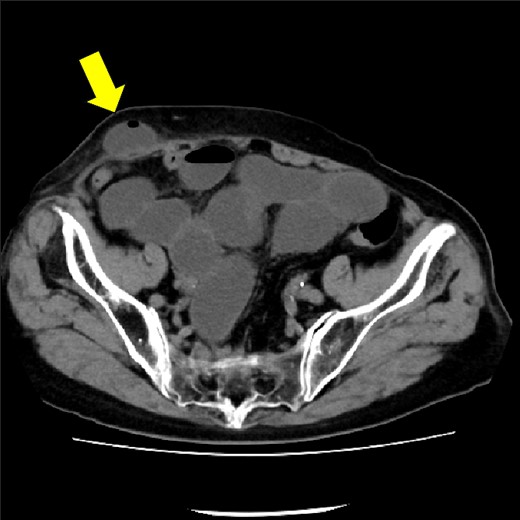

The patient was an 85-year-old woman with two pregnancies and two births. Her body mass index was 25 kg/m2. She had a history of hypertension, rheumatism, and open right pyeloplasty performed for stenosis of the right renal pelvic ureteric junction. A tumor in the right kidney was detected on an abdominal ultrasound examination and computed tomography (CT); the tumor size was about 30 mm (Fig. 1). A transperitoneal laparoscopic nephrectomy was performed. The operation time was 1 h and 52 min, and the blood loss was 10 ml. The surgery was completed without complications.

CT showing 30 mm right renal cell carcinoma. The arrow shows the tumor.